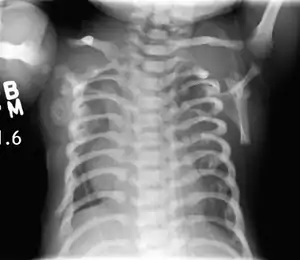

![]() | |

| CXR of a newborn with asphyxiating thoracic dysplasia. Note the short ribs. | |